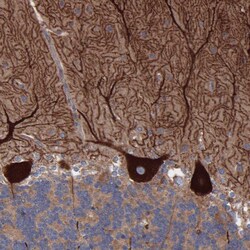

PA5-53560 IHC

Immunohistochemistry